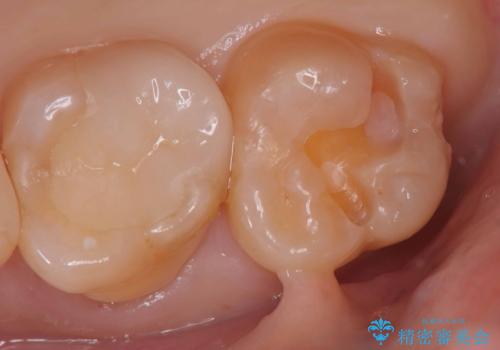

【セラミックインレー】咬合面のカリエス

- メンテナンス時に見つかった虫歯です。二次カリエスのリスクを下げる為に虫歯を除去後セラミックインレーで治療を行いました。

咬合面の溝が深く虫歯のリスクが大きい患者様です。

他の歯も咬合面に同じように虫歯ができて大きくなってしまった経験があることから今回は大きくそして深く進行する前に虫歯を除去しセラミックインレーで治療を行いました。